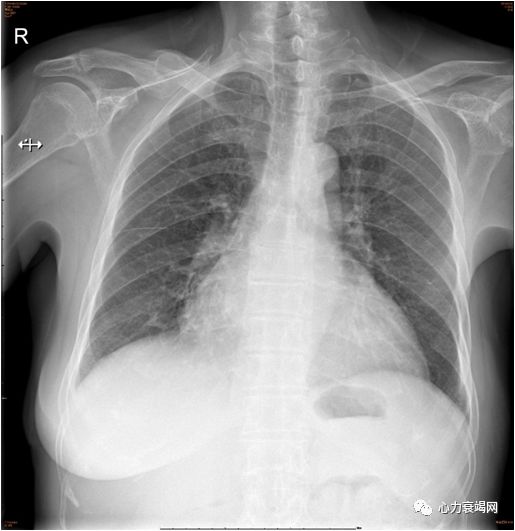

胸片

两肺纹理增多稍模糊,右侧胸膜反应,心影增大

患者超滤结束后,夜间能平卧,静息时不吸氧情况下无呼吸困难,心功能稳定,食欲明显改善,下肢水肿明显消退。

超滤后NT-proBNP水平从10434ng/L降至2519ng/L。超滤后复查胸片,两肺渗出,两侧胸腔积液明显改善。